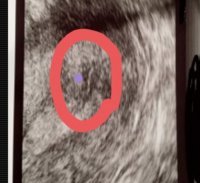

Hei! Jeg har vært hos gynekologen nå, etter å ha fått noen svak positive tester. Istede for å gå berserk med å teste, så tok hun blodprøver og ultralyd.

Hun så en fin og kjempe tykk slimhinne, og hun Ville stolt på testen, og si jeg var ca 4 uker, men for tidlig at det synes på ul. Hva synes dere her? Noen som har opplevd det samme?